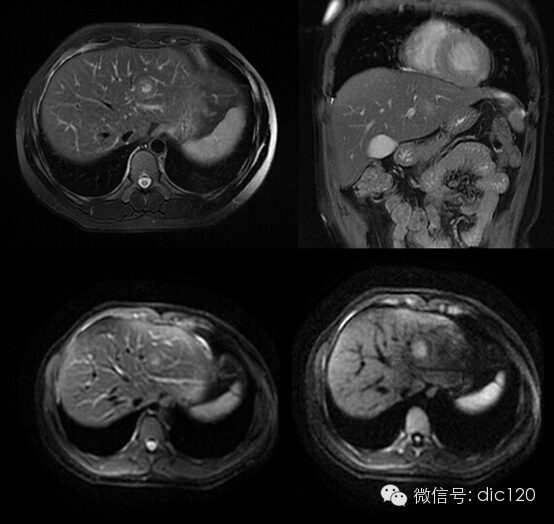

影像表現(xiàn):CT平掃與正常肝組織呈等密度,密度均勻,動(dòng)脈期病灶快速明顯均勻強(qiáng)化,中心見小片狀低密度影(瘢痕),門脈期及延遲期對比劑快速退出呈等密度,中央低密度影延遲強(qiáng)化。MRI腫塊T2WI為稍高信號(hào),中央高信號(hào)。動(dòng)態(tài)增強(qiáng)掃描動(dòng)脈期均顯著增強(qiáng),門脈期輕度增強(qiáng),延遲期瘢痕強(qiáng)化。

FNH具有離心性血液供應(yīng)及二條血液引流途徑。FNH的典型CT表現(xiàn)包括增強(qiáng)早期腫瘤呈彌漫均勻強(qiáng)化,在門靜脈期或門靜脈后期成等密度,病灶內(nèi)可見中心低密度瘢痕及輻射狀分隔,腫瘤周圍有薄而不完整的包膜樣血管。瘢痕是FNH 另一個(gè)重要影像學(xué)表現(xiàn),尤其是延遲掃描瘢痕強(qiáng)化為其特征。